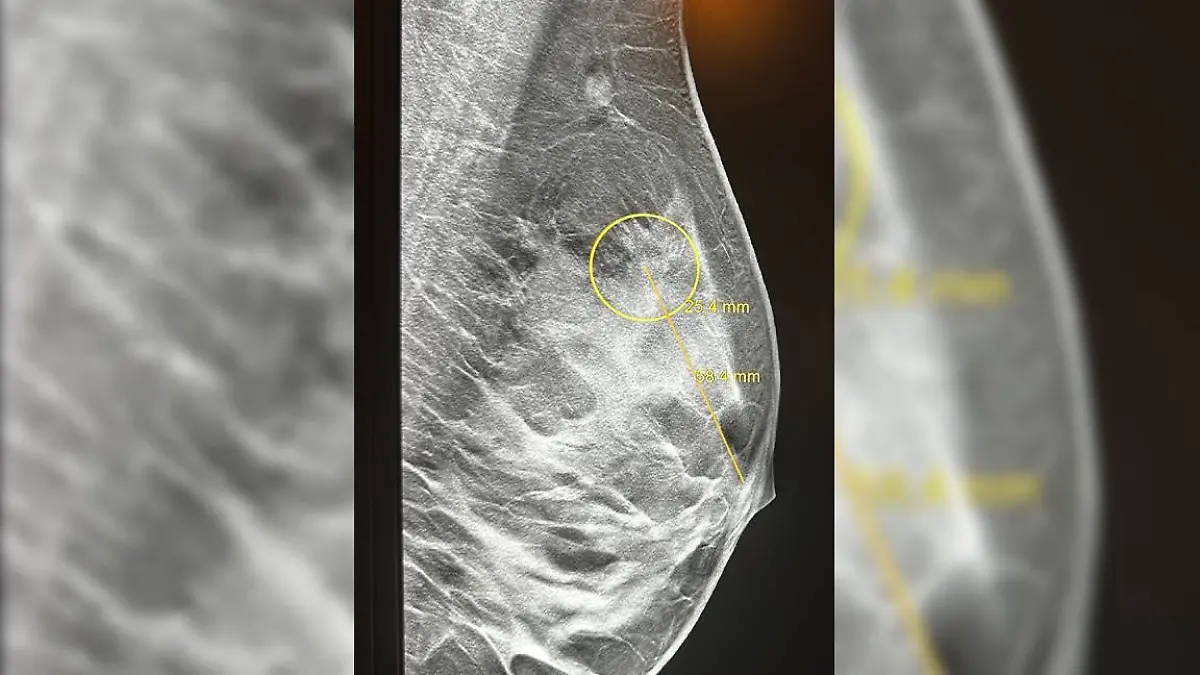

Sarah ist gelernte Krankenschwester. Nach einem Nachtdienst sitzt die heute 31-Jährige gedankenverloren auf der Toilette. Sie will noch schnell ihre Brust abtasten, wie sie es so oft tut. Doch dann der Schock: Irgendetwas fühlt sich falsch an. Sie kontaktiert ihre Frauenärztin. Es werden Tests gemacht. „Im Mai 2024 habe ich die Diagnose triple-negatives malignes Mammakarzinom bekommen”, erzählt Sarah Reimann im Gespräch mit RTL. Triple-negativer Brustkrebs gilt als sehr aggressiv, da er schneller wächst und stärker zu Metastasen und Rückfällen neigt. „Ich hatte Angst, am Brustkrebs zu sterben.”